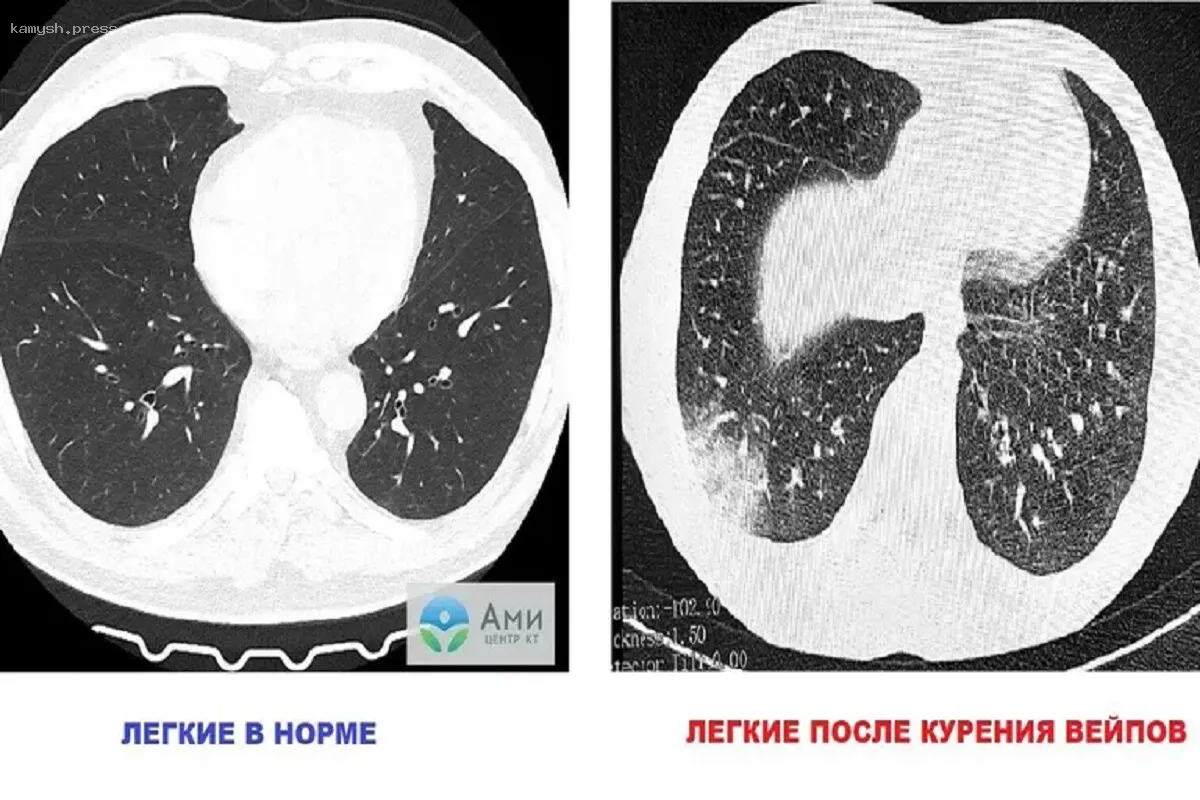

Исследования показали, что электронные сигареты могут спровоцировать острое воспаление легких – EVALI. При этом первые симптомы появляются спустя три месяца регулярного курения вейпов. При более продолжительном использовании болезни прогрессируют.

Как объяснил врач-онколог высшей квалификационной категории, торакальный хирург, кандидат медицинских наук Андрей Нефедов, со временем клетки, которые отвечают за защиту и очищение дыхательных путей, перестают выполнять свои функции. В результате токсины накапливаются в легких, вызывая воспаление и нарушения газообмена в альвеолах. Позднее это приводит к EVALI, которая проявляется одышкой, лихорадкой, болями в груди, тошнотой, рвотой и сильной усталостью, отметил врач в интервью «Известиям».